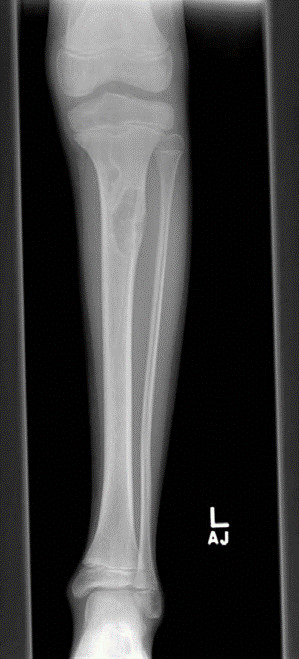

Lower limb Trauma Structured oral examination question 5 A 21-year-old motorcyclist was involved in a road tr…